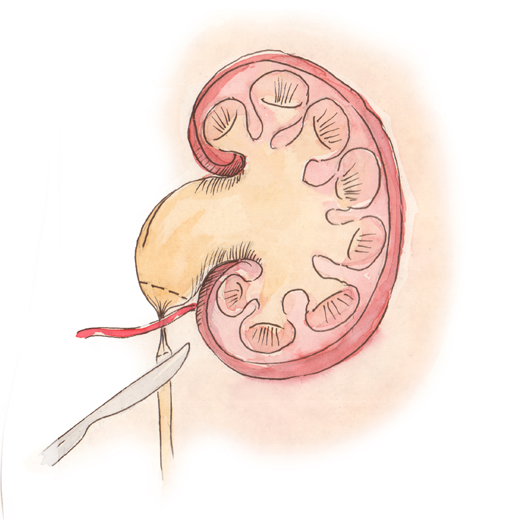

Интраренальная лоханка: рентгеновские снимки и примеры

Раздел: Фотоэссе